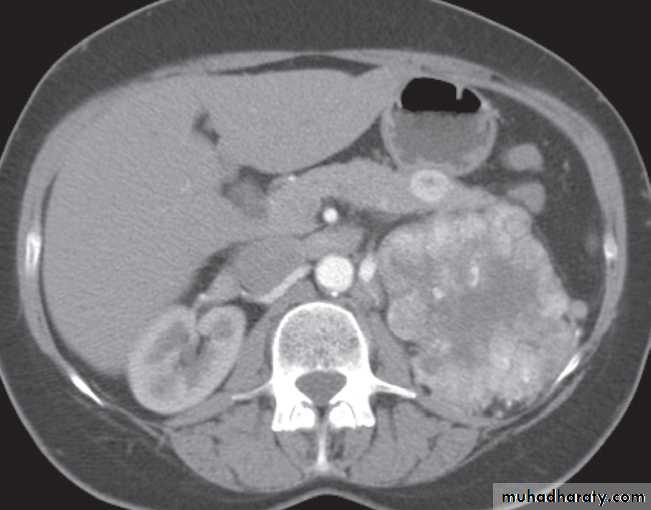

-Renal cell carcinomas are approximately spherical and often lobulated .With density similar to renal parenchyma or slightly less with often seen some areas of necrosis & calcification .

Staging of renal cell carcinoma is usually undertaken with CT, the current method of choice .

Wilms’ tumour is the likely diagnosis in a child with a renal mass. These lesions are frequently large and may contain stippled calcification